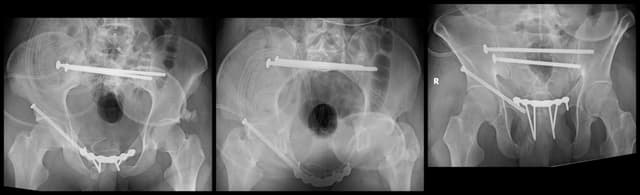

Imaging

Post-op